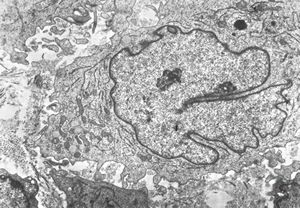

M, 11y. | mycosis fungoides v.s. - cerebriform nucleus of Sézary cell

F, 57y. | mycosis fungoides … cerebriform nucleus of Sézary cell

F, 37y. | mycosis fungoides … cerebriform nucleus of Sézary cell

M, 70y. | mycosis fungoides - Sézary cell